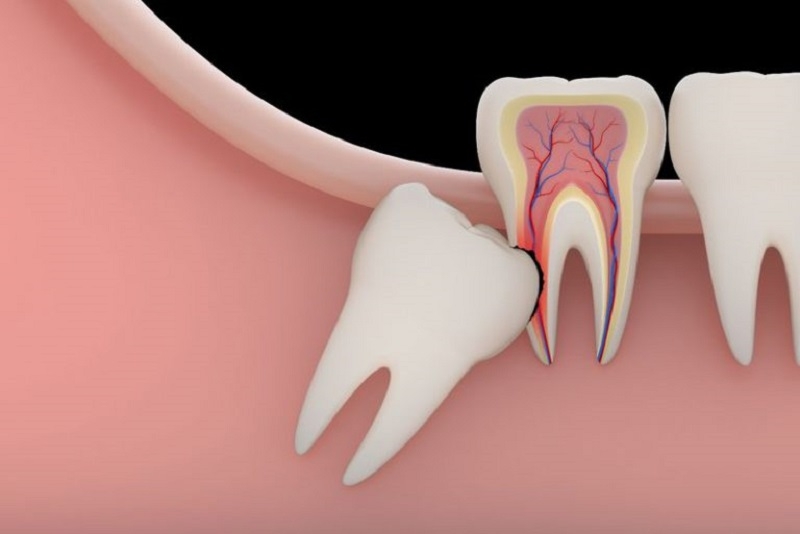

Dấu hiệu răng mọc ngầm Răng mọc ngầm là răng mọc nằm sâu ở bên trong ổ xương hàm hoặc ở vị trí dưới nướu

Răng mọc ngầm có đặc điểm chính là răng mọc nằm sâu ở bên trong ổ xương hàm hoặc ở vị trí dưới nướu nhưng không mọc lên cung hàm được. Các chiếc răng mọc ngầm hoàn toàn có thể mọc đầy đủ nguyên vẹn như các răng bình thường khác. Hoặc đôi khi nó có thể chỉ ở dạng nang.

Trong thực tế, tình trạng răng mọc ngầm có thể xảy ra ở mọi răng vĩnh viễn của mỗi người. Tuy nhiên, răng mọc ngầm thường gặp nhất đó chính là răng khôn, hay còn được gọi là răng số 8. Nguyên do của tình trạng này là vì răng khôn là những chiếc răng mọc sau cùng trên cung hàm. Trong khi các răng khác đã mọc đầy đủ và đúng vị trí thì nó vẫn chưa mọc lên. Thế nên không còn đủ khoảng trống thuận lợi để răng khôn mọc bình thường và thậm chí là không thể tách nướu trồi lên. Không chỉ có vậy, những chiếc răng số 8 này thường hay mọc lệch lạc, mọc sai vị trí hay mọc xiên, mọc ngang,...